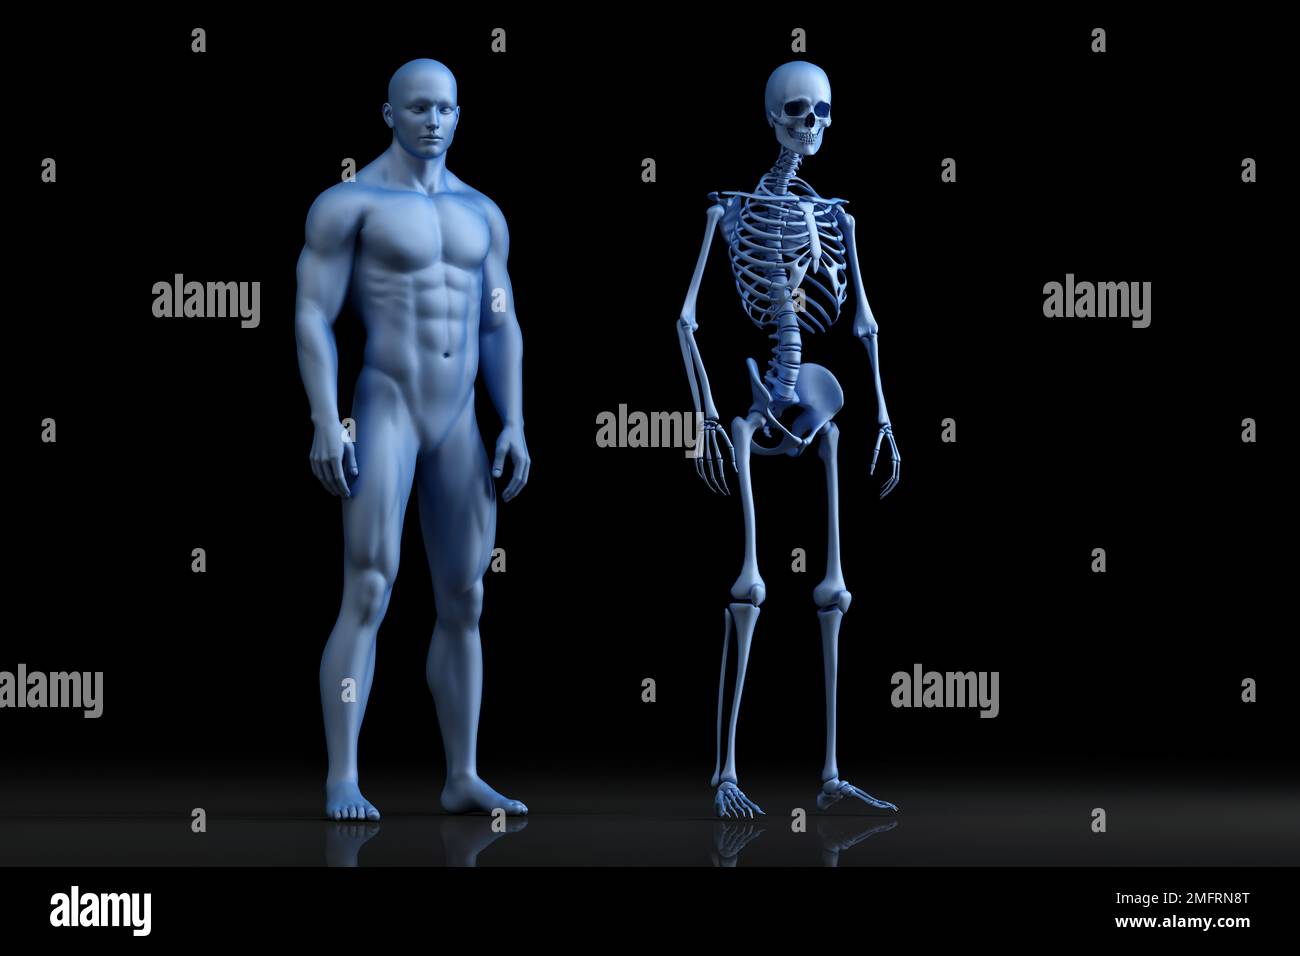

RF2ME385Y–Menschliches männliches Skelett mit Vorderansicht des Körpers 3D-Darstellung mit Kopierraum und DNA-Hintergrund. Anatomie, Medizin und Gesundheitswesen, Biologie, ich